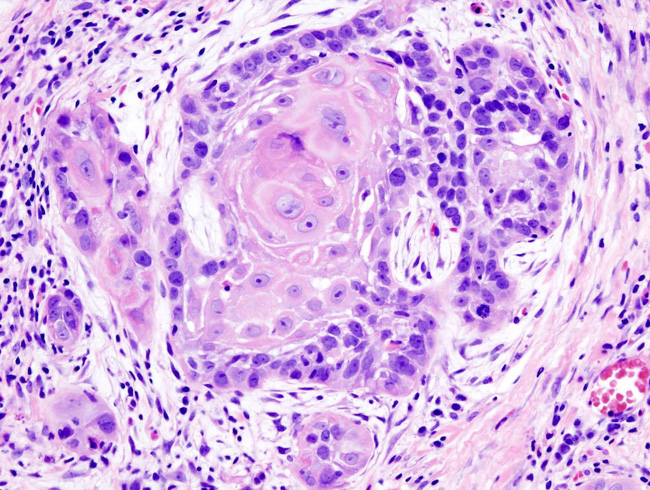

TS Pimple Popper hay còn có tên gọi khác là Sandra Lee trở nên nổi tiếng bằng cách đăng tải hình ảnh đồ họa của những nốt mụn thô đặc biệt. Gần đây, vị bác sĩ chuyên khoa da liễu đến từ Los Angeles này đăng một bức ảnh về một thứ khác biệt: Vết sưng phồng, đỏ ửng trên đầu của một người đàn ông cảnh báo loại ung thư da có tên là keratoacanthoma. [Cách nhận biết và phòng ngừa ung thư da]

Trong chú thích của mình, BS Lee giải thích đây là trường hợp ung thư biểu mô tế bào vảy (một loại ung thư da bắt đầu ở lớp giữa và lớp ngoài của da) không nguy hiểm đến tính mạng, nhưng nó có thể phát triển nhanh nếu không được điều trị.

Ung thư biểu mô tế bào vảy dễ phát triển do tiếp xúc quá nhiều với ánh nắng

Ung thư biểu mô tế bào vảy là sự tăng trưởng không kiểm soát của những tế bào bất thường, phát sinh trong các tế bào vảy – tế bào hình thành các lớp trên của da. Ung thư biểu mô tế bào vảy thường trông giống như các mảng đỏ có vảy, vết thương hơ, mụn cóc hoặc khối u có phần trung tâm lõm xuống. Sự phát triển của chúng không chỉ gây mất thẩm mỹ mà đôi khi còn gây tử vong.

Theo Webmd, ung thư biểu mô tế bào vảy thường có các triệu chứng phổ biến như: Nốt đỏ, chắc; mảng tróc vảy, phẳng và đau; mảng thô ráp, có vảy ở trên môi, có thể phát triển thành vết loét mở; mảng màu đỏ, đau hoặc thô ráp trong miệng; mảng màu đỏ, nổi đau như mụn cóc [chữa mụn cóc tại nhà] trên hoặc bên trong hậu môn hoặc bộ phận sinh dục.

Theo Mayoclinic, ung thư biểu mô tế bào vảy thường được gây ra bởi sự tiếp xúc quá mức với tia UV từ mặt trời hoặc giường tắm nắng. Đó là lý do tại sao sự tăng trưởng ung thư như bức ảnh của Tiến sĩ Lee thường xuất hiện trên các vùng cơ thể có nhiều ánh nắng mặt trời, như đỉnh đầu bị hói của người đàn ông này.